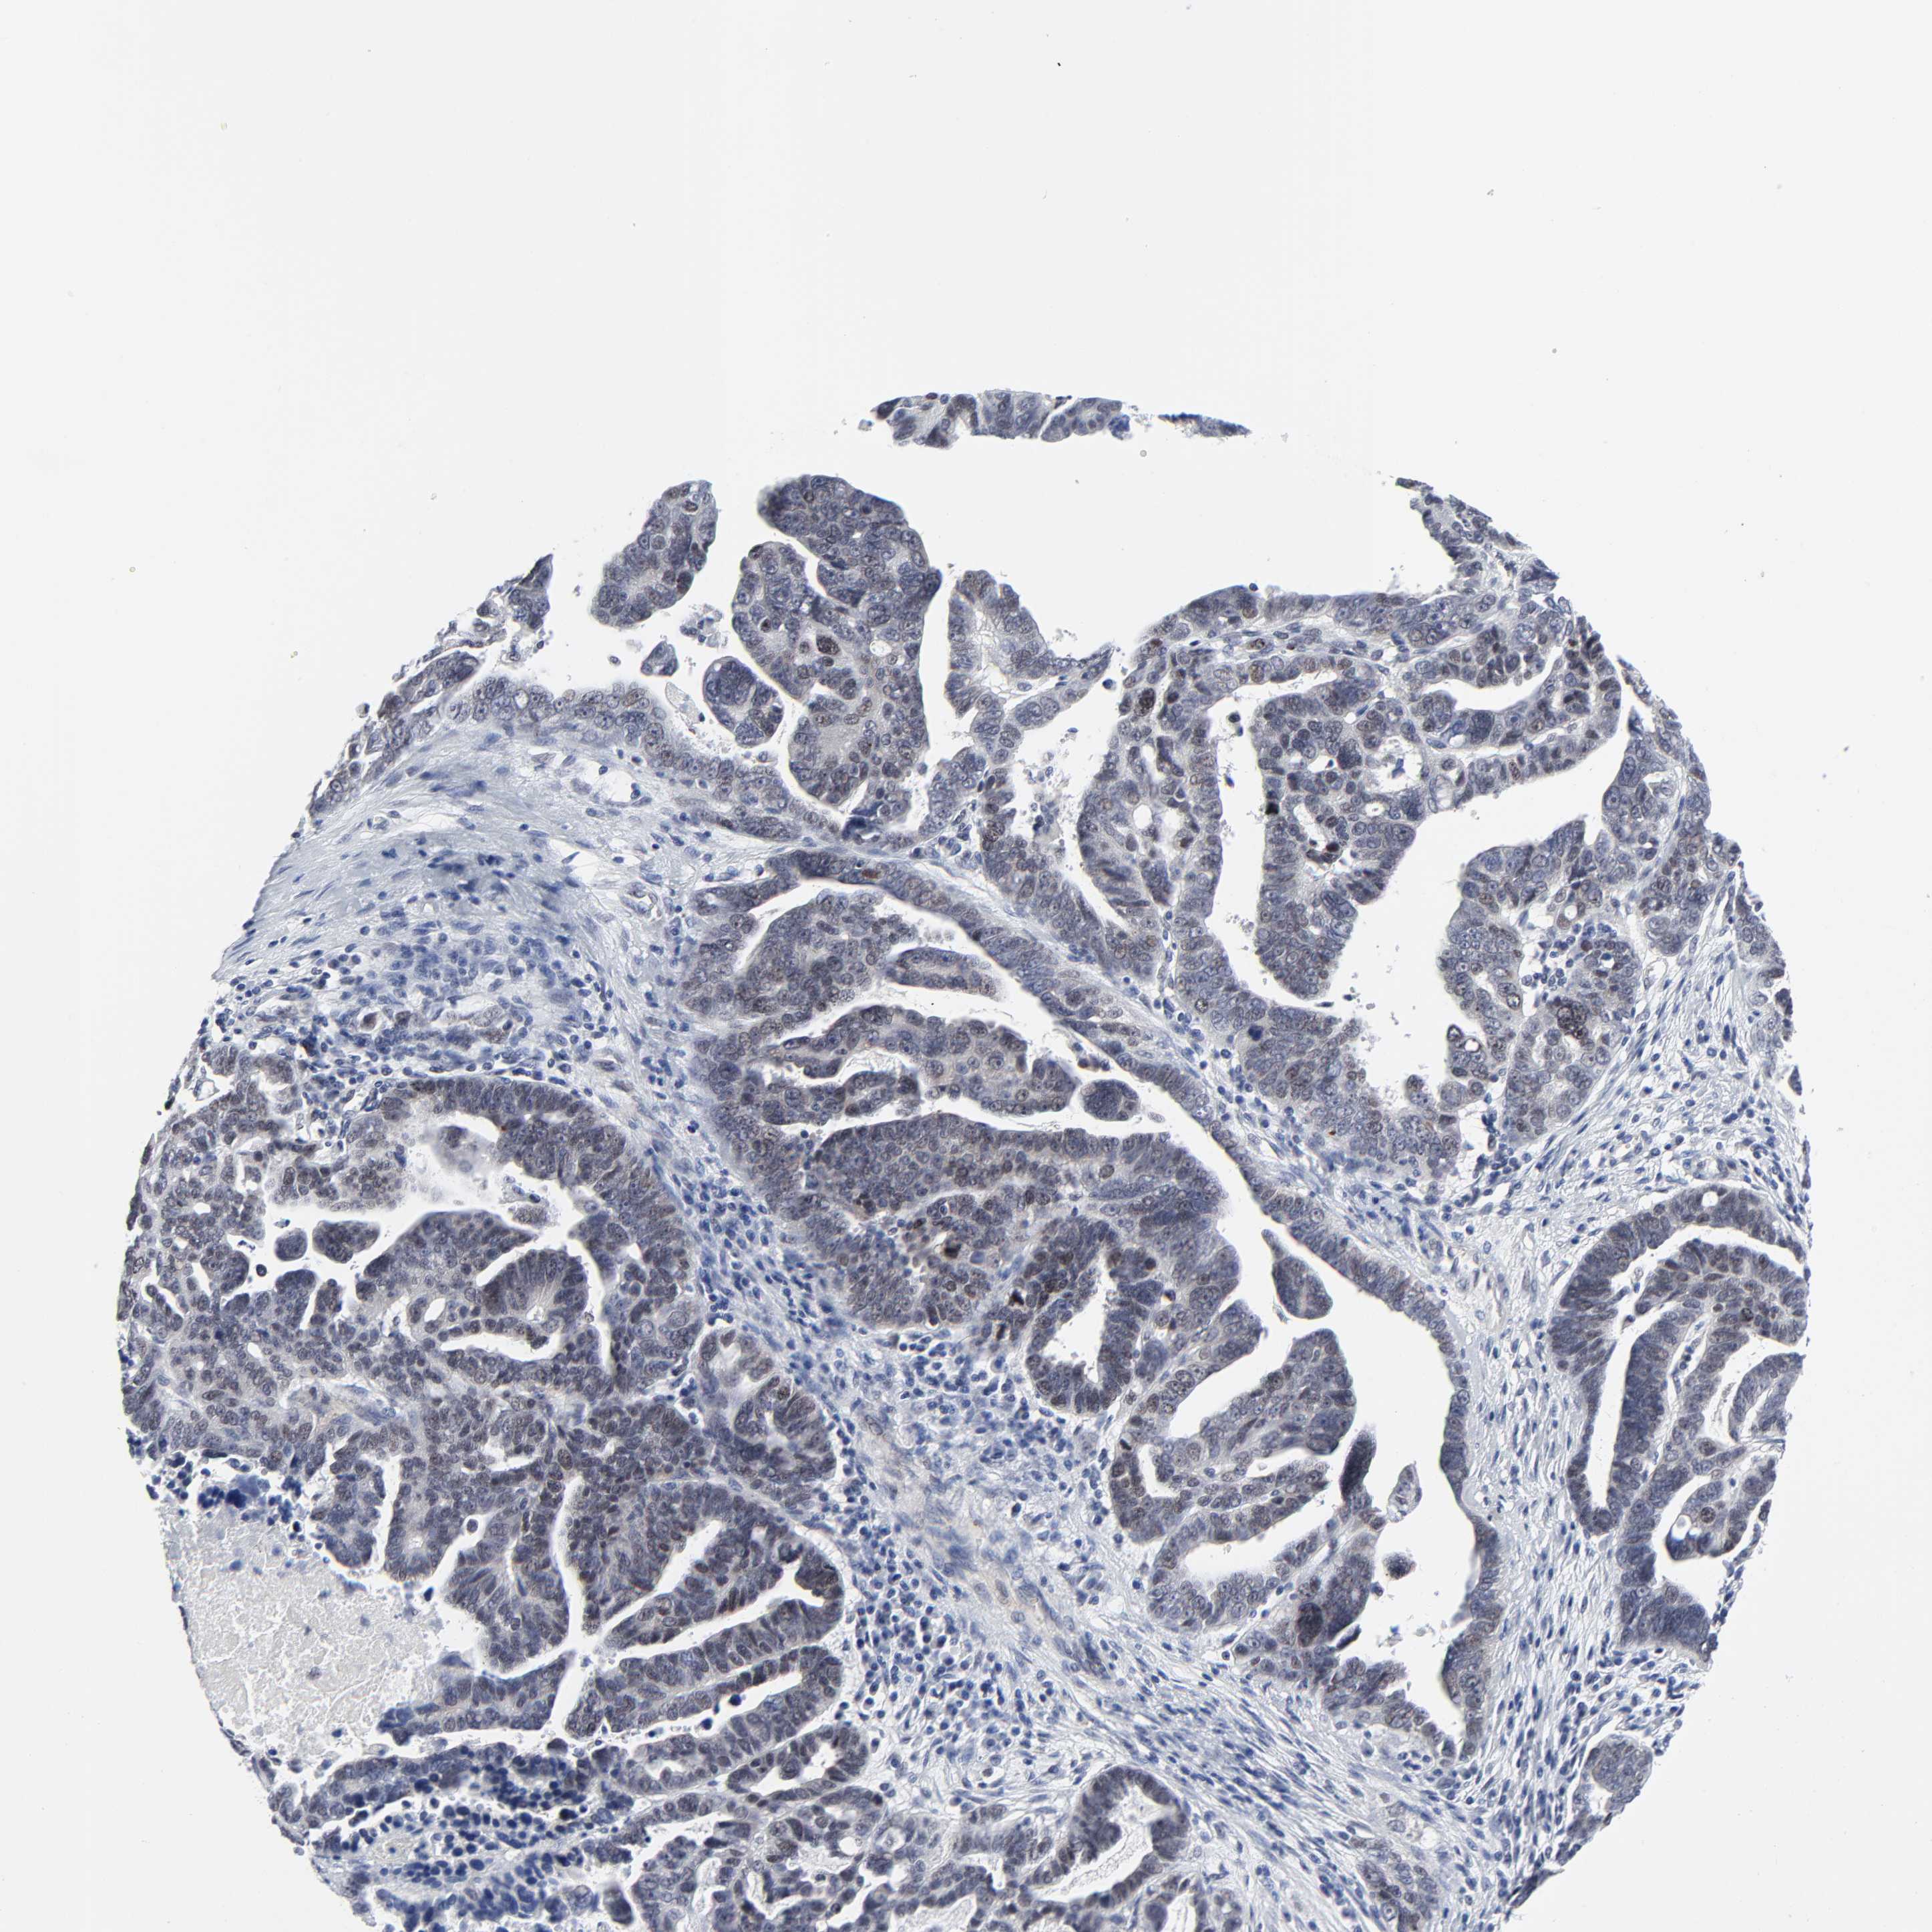

OVARIAN CANCER - Protein expressioni

A mouse-over function shows sample information and annotation data. Click on an image to view it in a full screen mode. Samples can be filtered based on level of antibody staining by selecting one or several of the following categories: high, medium, low and not detected. The assay and annotation is described here.

Note that samples used for immunohistochemistry by the Human Protein Atlas do not correspond to samples in the TCGA dataset.

Antibody stainingi

Antibody staining in the annotated cell types in the current human tissue is reported as not detected, low, medium, or high, based on conventional immunohistochemistry profiling in selected tissues. This score is based on the combination of the staining intensity and fraction of stained cells.

Each image is clickable and will lead to virtual microscopy that enables deeper exploration of all samples and also displays staining intensity scores, fraction scores and subcellular localization as well as patient and tissue information for each sample.

Antibody HPA003145

Staining

High

Medium

Low

Not detected

Intensity

Strong

Moderate

Weak

Negative

Quantity

>75%

75%-25%

<25%

None

Location

Nuclear

Cytoplasmic/membranous

Cytoplasmic/membranous,nuclear

Carcinoma, endometroid

Cystadenocarcinoma, serous, NOS

Cystadenocarcinoma, mucinous, NOS